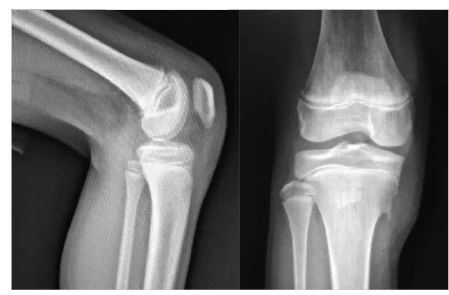

看病历▼

男,11岁,胫骨前结节稍肿胀,右膝疼痛两月余,按压疼痛,胫骨结节下部与骨干分离。

X线片可显示胫骨结节骨软骨炎患者骨质及软组织的异常改变,是诊断胫骨结节骨软骨炎颇有价值的方法,对一些早期及可疑患者可进一步做CT或MRI检査